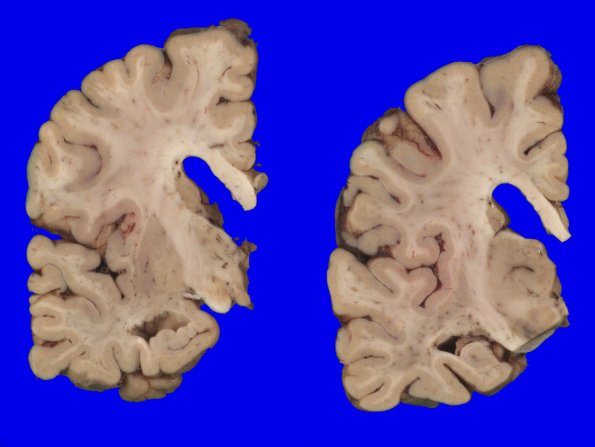

Coronal slicing revealed mild dilatation of the lateral ventricles with rounding of the angles, increased space in the inferior horns, and small hippocampi.